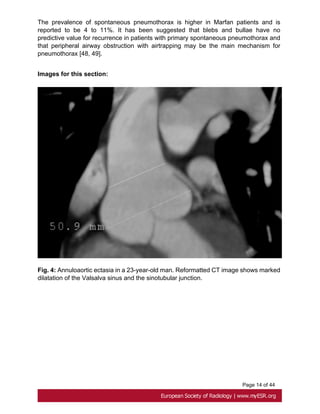

• Annuloaortic ectasia

Progressive sinus enlargement is present in 50 to 60% of adults at the mean age of 35

years with Marfan syndrome, with a greater prevalence in males than in females [9]. It

usually begins with dilatation of the aortic sinuses, which progress into the sinotubular

junction and into the aortic annulus. Fig. 4 on page 14

The prevalence of spontaneous pneumothorax is higher in Marfan patients and is

reported to be 4 to 11%. It has been suggested that blebs and bullae have no

predictive value for recurrence in patients with primary spontaneous pneumothorax and

that peripheral airway obstruction with airtrapping may be the main mechanism for

pneumothorax [48, 49].

Images for this section:

Fig. 4: Annuloaortic ectasia in a 23-year-old man. Reformatted CT image shows marked

dilatation of the Valsalva sinus and the sinotubular junction.

Page 14 of44 The prevalence of spontaneous pneumothorax is higher in Marfan patients and is reported to be 4 to 11%. It has been suggested that blebs and bullae have no predictive value for recurrence in patients with primary spontaneous pneumothorax and that peripheral airway obstruction with airtrapping may be the main mechanism for pneumothorax [48, 49]. Images for this section: Fig. 4: Annuloaortic ectasia in a 23-year-old man. Reformatted CT image shows marked dilatation of the Valsalva sinus and the sinotubular junction.